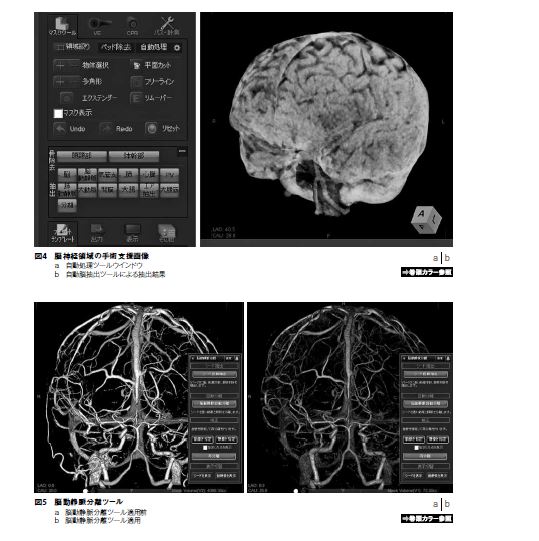

自動処理ツールは現在多くのWSで実装されている。機能の具体性としては、人体構造における血管・臓器の抽出、更には臓器構造の分割機能である。冠動脈や肝臓の区域分割では多くのユーザーが恩恵に預かっていると思われる。ziostation2では、脳神経領域において2つの自動処理ツールが実装される。一つは、頭部画像から脳実質のみを抽出する自動脳抽出ツールである。脳神経領域の手術支援画像では、病変へのアプローチにおいて脳表の状態を表示しなければならない。この場合、主に単純CTから脳実質を抽出して血管構造とのfusion表示を行う。脳実質は頭蓋骨とのCT値に大きな差があり骨との分離は容易であるが、頭皮とは骨を挟んではいるがその分離は意外に容易ではない。分離はいくつかの手順を踏めば数分で可能だが、構造だけにいわゆるコスパ的に結構なストレスを感じる。それが、自動脳抽出ツールではワンクリックで精度良く抽出が実現できるため、大変重宝するツールである。脳表の表示は、脳神経領域の手術支援画像において、どの疾患・症例にも共通したものであるため、とても有用なツールと考える(図4)。

もう一つのツールは、脳動静脈分離ツールである。前項で述べたとおり、動静脈の分離は様々なマスクツールの機能で実現可能である。ただし、解剖学的にはかなりの専門性が必要となる。また、良い意味で手間が掛けられる反面、処理時間もそれなりに要する。これまで、3D画像処理は手間暇を掛けるのが当然の認識であったが、ワークフローへの組み入れやすさ、働き方改革に即した機能も現在のWSには求められるツールと推察する。脳動静脈分離ツールでは初めにシード抽出で大まかな分離が行われる。その後、自動分離を実行すると、シードを元に連続性や形態の認識機能も働き、抹消血管まで分離が進む。現在、分離精度はかなり向上しており、シード抽出など脳動静脈分離ツールの処理段階で解剖学的知識をもとに手を加えると、個々で異なる血管形態にも高精度で分離が可能となる。従来のマスクツールのみでの分離よりも、手間を掛けずに同様の精度を担保することが可能となっている(図5)。